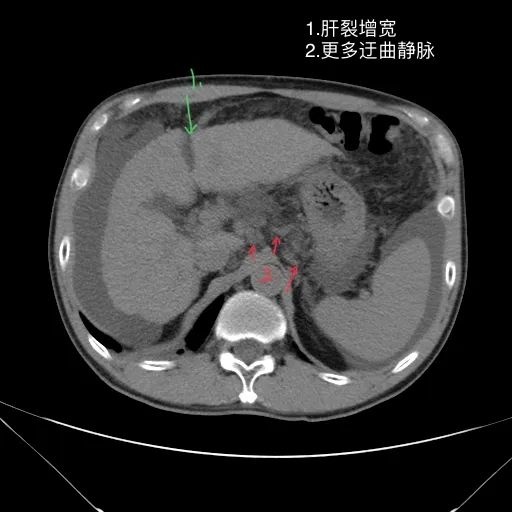

肝脏缩小,包膜凹凸不平,肝裂增宽,各叶比例失衡,肝实质密度不均,肝S4小片低密度影,约cm;胆囊不大,其内未见异常密度影,胆道系统未见扩张;胰腺、脾脏形态、密度、大小未见异常;双肾上腺及双肾形态、密度、大小未见异常,双输尿管未见扩张,膀胱充盈良好,壁光滑,其内未见异常密度影;前列腺未见异常;胃肠道未见充盈,壁未见明确增厚,食管胃底多发迂曲、增粗血管,腹部及腹膜后未见肿大淋巴结;腹水。

1.肝硬化失代偿表现(腹水,食管胃底静脉曲张)。

如上是肝硬化失代偿的典型表现。但没有门脉增宽和脾大表现。此外肝S4的小片低密度影除考虑为囊肿或镰旁假病灶外,还需警惕肿瘤?

除了观察肝硬化相关表现外,还应根据看片顺序继续观察胆囊 胰腺 脾脏 泌尿及生殖系统,最后别忘记主动脉及周围腹膜后结构,骨质及肌肉。